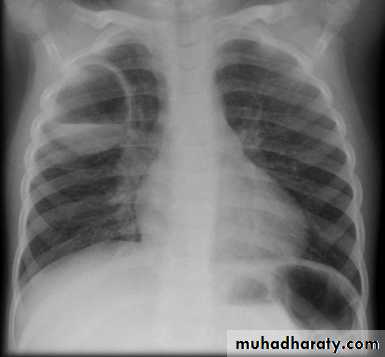

Routine CXR: is PA known as frontal view with optional lateral view.

Both should exposed in full insp. And patient in upright position.Films taken in exp. Are difficult to interpret because:

• 1- hazy lung base.

• 2- heart shadow increase in size.

• 1- trace the diaphragm: the upper surface of diaphragm should be clearly visible from CPA to other, except when heart and diaphragm in contact with diaphragm.

On good insp., the dome of rt. Hemidiaphragm at level of ant. End of 6th rib.

The rt. Hemidiaphragm being up to 2.5 cm higher than the left.

8- assess technical quality of the film: correctly exposed routine PA CXR is one in which the ribs and spine behind the heart can be identified but lung not overexposed.straight film is one where the medial ends of clavicles are equidistant from thoracic verteb.